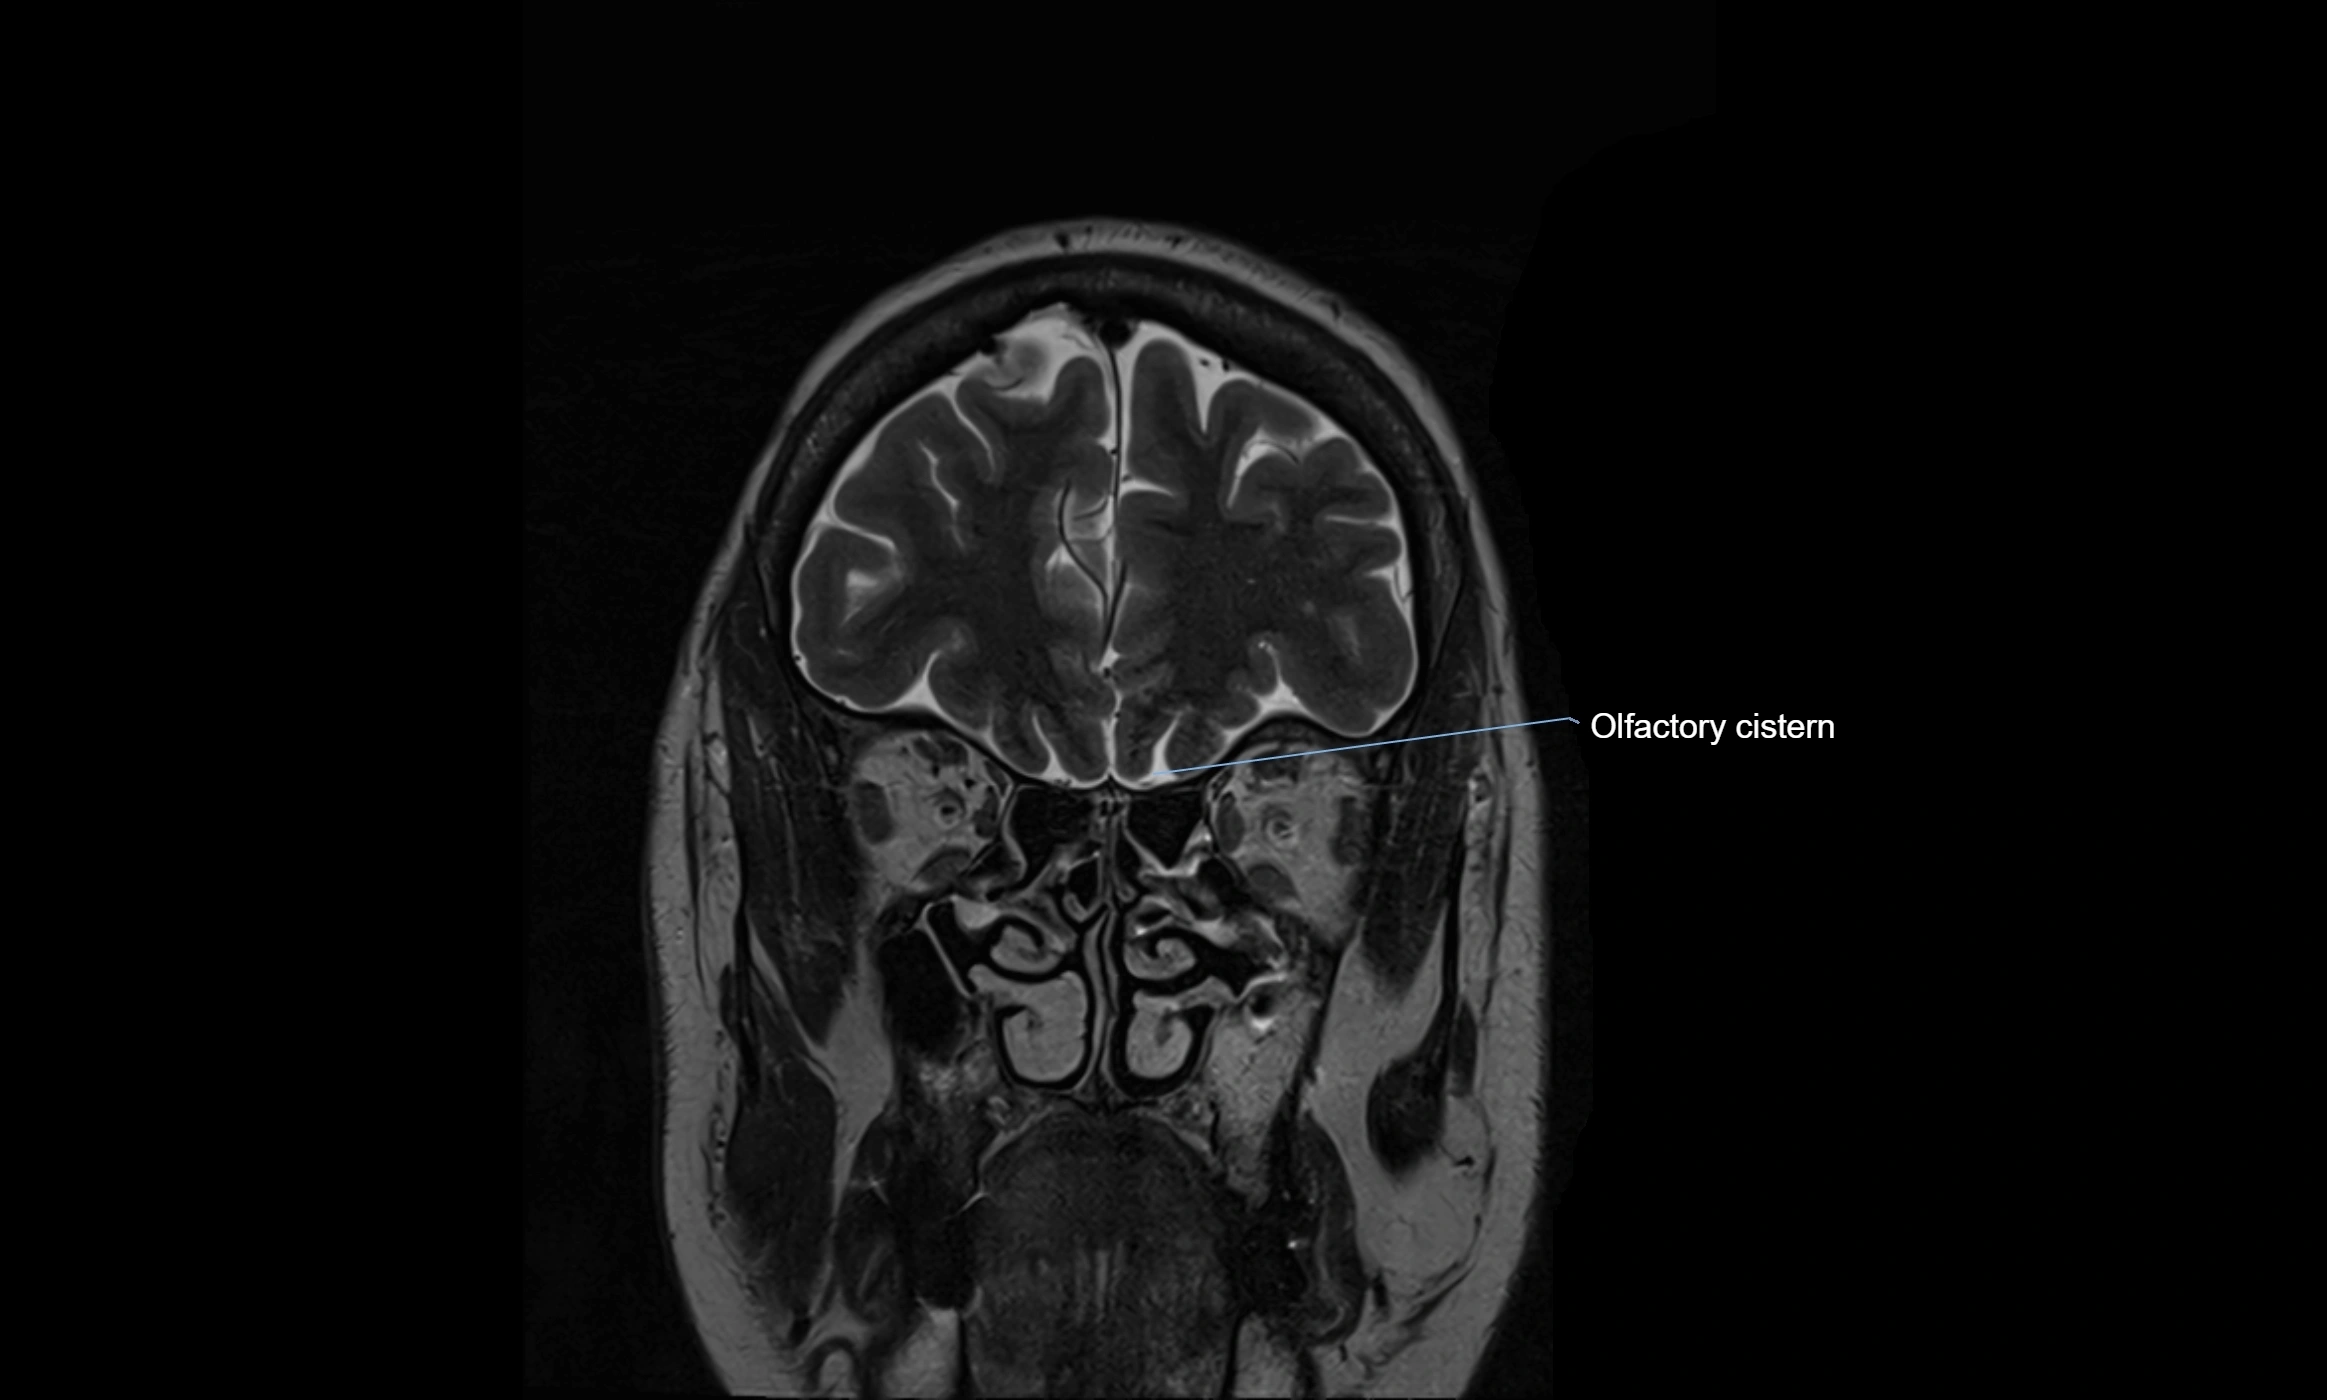

MRI images

image